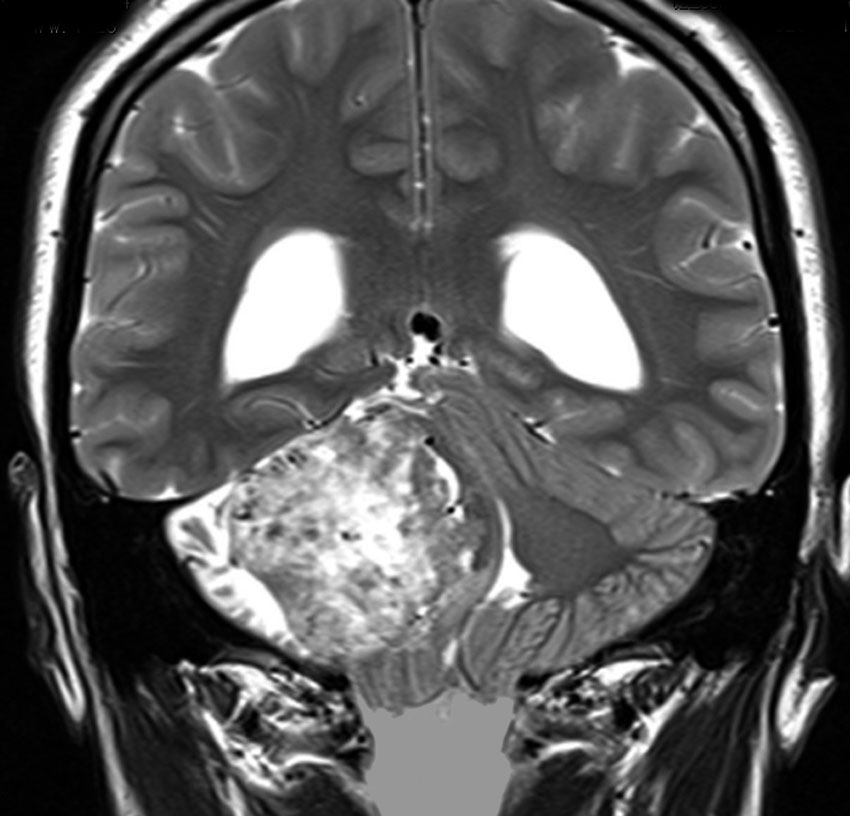

この腫瘍は脳幹部変形がとても強く,大きいので手術摘出するしか選択肢はありません

- 脳幹部の変形が高度な大きな腫瘍になると手術するしかありません

- 4cmを超えると危険だと考えてください

- のう胞性(腫瘍の内部がほとんど液体)のものは4cmを超えても手術は危なくないです

- 巨大な充実性の聴神経腫瘍の手術では命をなくすリスクもあるものです

聴神経腫瘍でまず手術が必要なのは巨大なものです。この4枚の写真は私が実際に手術をした患者さんのものです。脳幹部という脳の最も大切なところが腫瘍によって圧迫されて変形しているのが特徴です。右上のものはのう胞性腫瘍なので大きさの割に手術のリスクは高くありませんが,左上のものは実質性で出血性のものですごくリスクが高い手術でした。左下のものは普通のリスク。右下のものは超高難易度のものです。